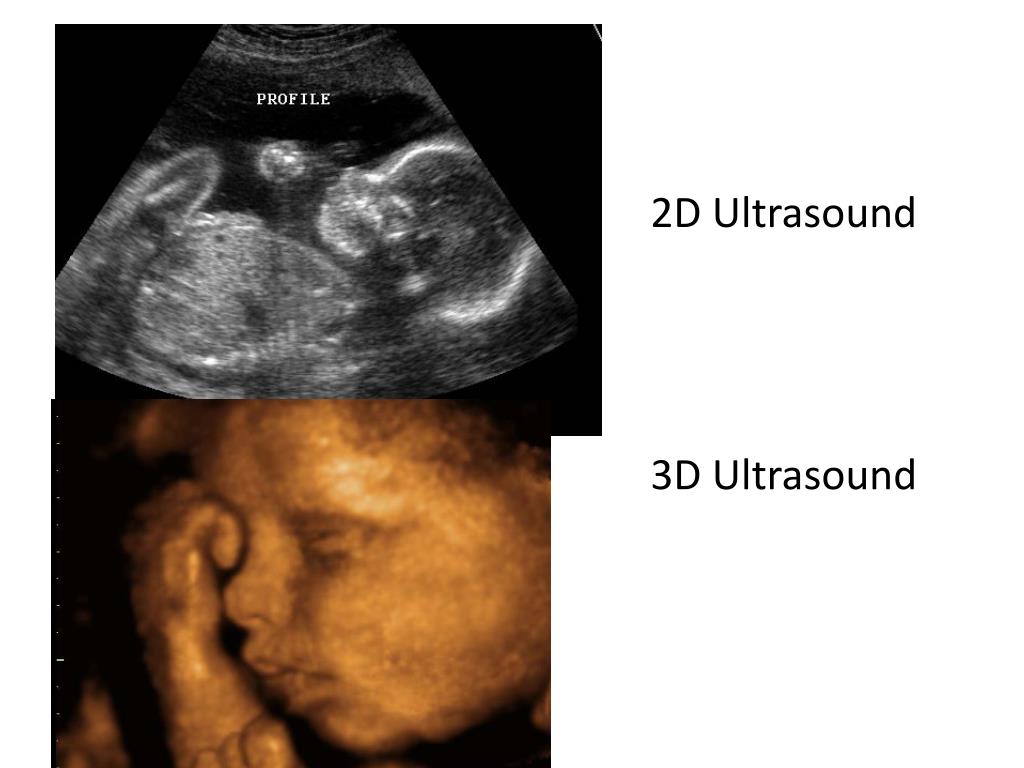

21. Ultrasound Another common energy source is ultrasound (echosonography), which developed out of research performed by the Navy during World War II. Ultrasonography uses pulses of high-frequency sound waves rather than ionizing radiation to image body structures. As each sound wave encounters tissues in a patient’s body, a portion of the wave is reflected and a portion continues.

22. The time required for the echo to return is proportional to the distance into the body at which it is reflected; the amplitude (intensity) of a returning echo depends on the acoustical properties of the tissues encountered and is represented in the image as brightness. The system constructs two-dimensional images by displaying the echoes from pulses of multiple adjacent one-dimensional paths. Such images can be stored in digital memories or recorded on videotape and then displayed as television (raster-display) images.

23. 2D Ultrasound 3D Ultrasound